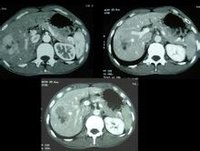

肝內血管瘤CT檢查結果

肝內血管瘤CT檢查結果是:

◆平掃:肝內低密度區輪廓清晰,密度均勻,或病變區內有更低的密度區,代表血栓機化,或纖維分隔,少數可見到鈣化。

◆增強後立即出現邊緣性增強,也有少數的患者在開始強化的時候並不出現在邊緣,可自中央開始,大多數呈團狀造影劑充填。

◆在連續掃描中主要表現的是造影劑自邊緣慢慢的向中央延伸,或者是多數的增強病灶相互的融合,也就是說造影劑在瘤樣的擴張的血管內彌散,是CT診斷肝內血管瘤的可靠的表現。

◆延遲掃描出現等密度或高密度,其中可伴有或無低密度區。這是肝內血管瘤與其他肝內占位性病變鑑別的重要徵象。尤其是與肝癌鑑別時,必須延遲5~l0分鐘再次掃描以觀察病灶的充盈情況,絕大多數肝內血管瘤在延遲掃描後均有不同程度造影劑充盈。